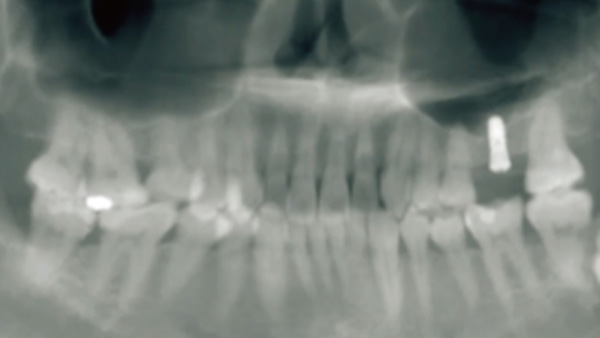

精度高

距離偏差≤0.5mm,角度偏差≤1°

覆蓋所有牙位、即刻種植、即拔即種、全口無牙頜種植